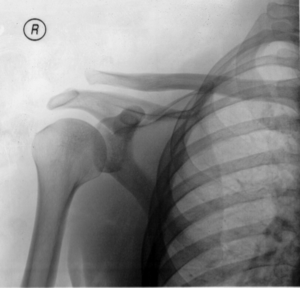

| A Separated Shoulder XRay modified to easily show bones. Notice the separation between the end of the collarbone and the scapula. | |

Diagnosis is based on physical examination and an x-ray. A separated shoulder occurs because of a direct blow to the AC joint or a fall on the elbow that forces the head of the humerus into the AC joint. Furthermore, AC separation can be identified point tenderness, pain at the AC joint with cross-arm adduction, and pain relief with an injection of a local anesthetic. The cross-arm adduction will produce pain specifically at the AC joint and will be done by elevating the arm to a 90° angle, flexing the elbow to a 90° angle, and adducting the arm across the chest. The pain in the shoulder is hard to pinpoint of the innervation of the AC joint and the glenohumeral joint. An injury to the AC joint will result in pain over the AC joint, in the anterolateral neck and in the region in the anterolateral deltoid.

In a Type III AC separation both acromioclavicular and coracoclavicular ligaments are torn without significant disruption of the deltoid or trapezial fascia.[4] A significant bump, resulting in some shoulder deformity, is formed by the lateral end of the clavicle. This bump, caused by the clavicle's dislocation, is permanent. The clavicle can be moved in and out of place on the shoulder. A radiographic examination, will show the results as abnormal. Pain with motion can be severe.